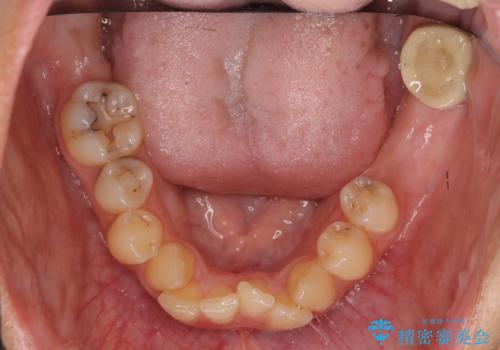

虫歯が多数、また奥歯も欠損してしまっていました。

左下の親知らず、左上の小臼歯が残根状態で一本抜いたほかは抜かずに矯正しました。

予算的に右下の一番奥のインプラントは難しかったため、できる限り対応しました。